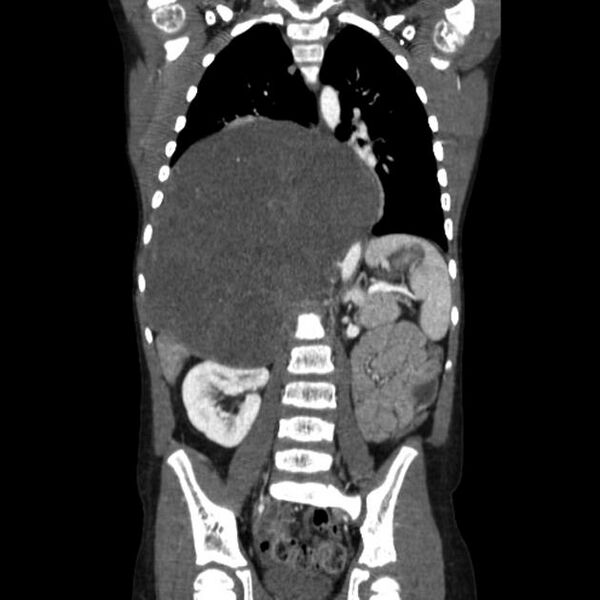

Ганглионевромы образуются как из центральной, так и из периферической нервной системы, являясь опухолью из зрелых клеток нервных ганглиев. Они возникают на фоне нарушения закладки клеток симпатической нервной системы во внутриутробном периоде. Часто локализуются в заднем средостении, мозговом веществе надпочечников, забрюшинном пространстве, полости малого таза и нередко прорастают в позвоночный канал с формированием паравертебрального и экстрамедуллярного компонентов[5]. Патогенез до конца не изучен[1].

Методы визуализации неспецифичны. Это методы, использующиеся для выявления и диагностики других злокачественных и доброкачественных образований (УЗИ, МСКТ, МРТ органов грудной клетки и брюшной полости)[8]. Диагноз окончательно устанавливается на основании результатов морфологического исследования послеоперационного материала при хирургическом лечении[6].

Возможно проведение радикального хирургического лечения, при котором лучевая и химиотерапия в дальнейшем не требуются. Решение об оперативном вмешательстве рекомендуется принимать в индивидуальном порядке с учетом всех имеющихся данных о состоянии здоровья пациента, топографии ганглионевромы и её характеристик, полученных при компьютерной томографии[2].